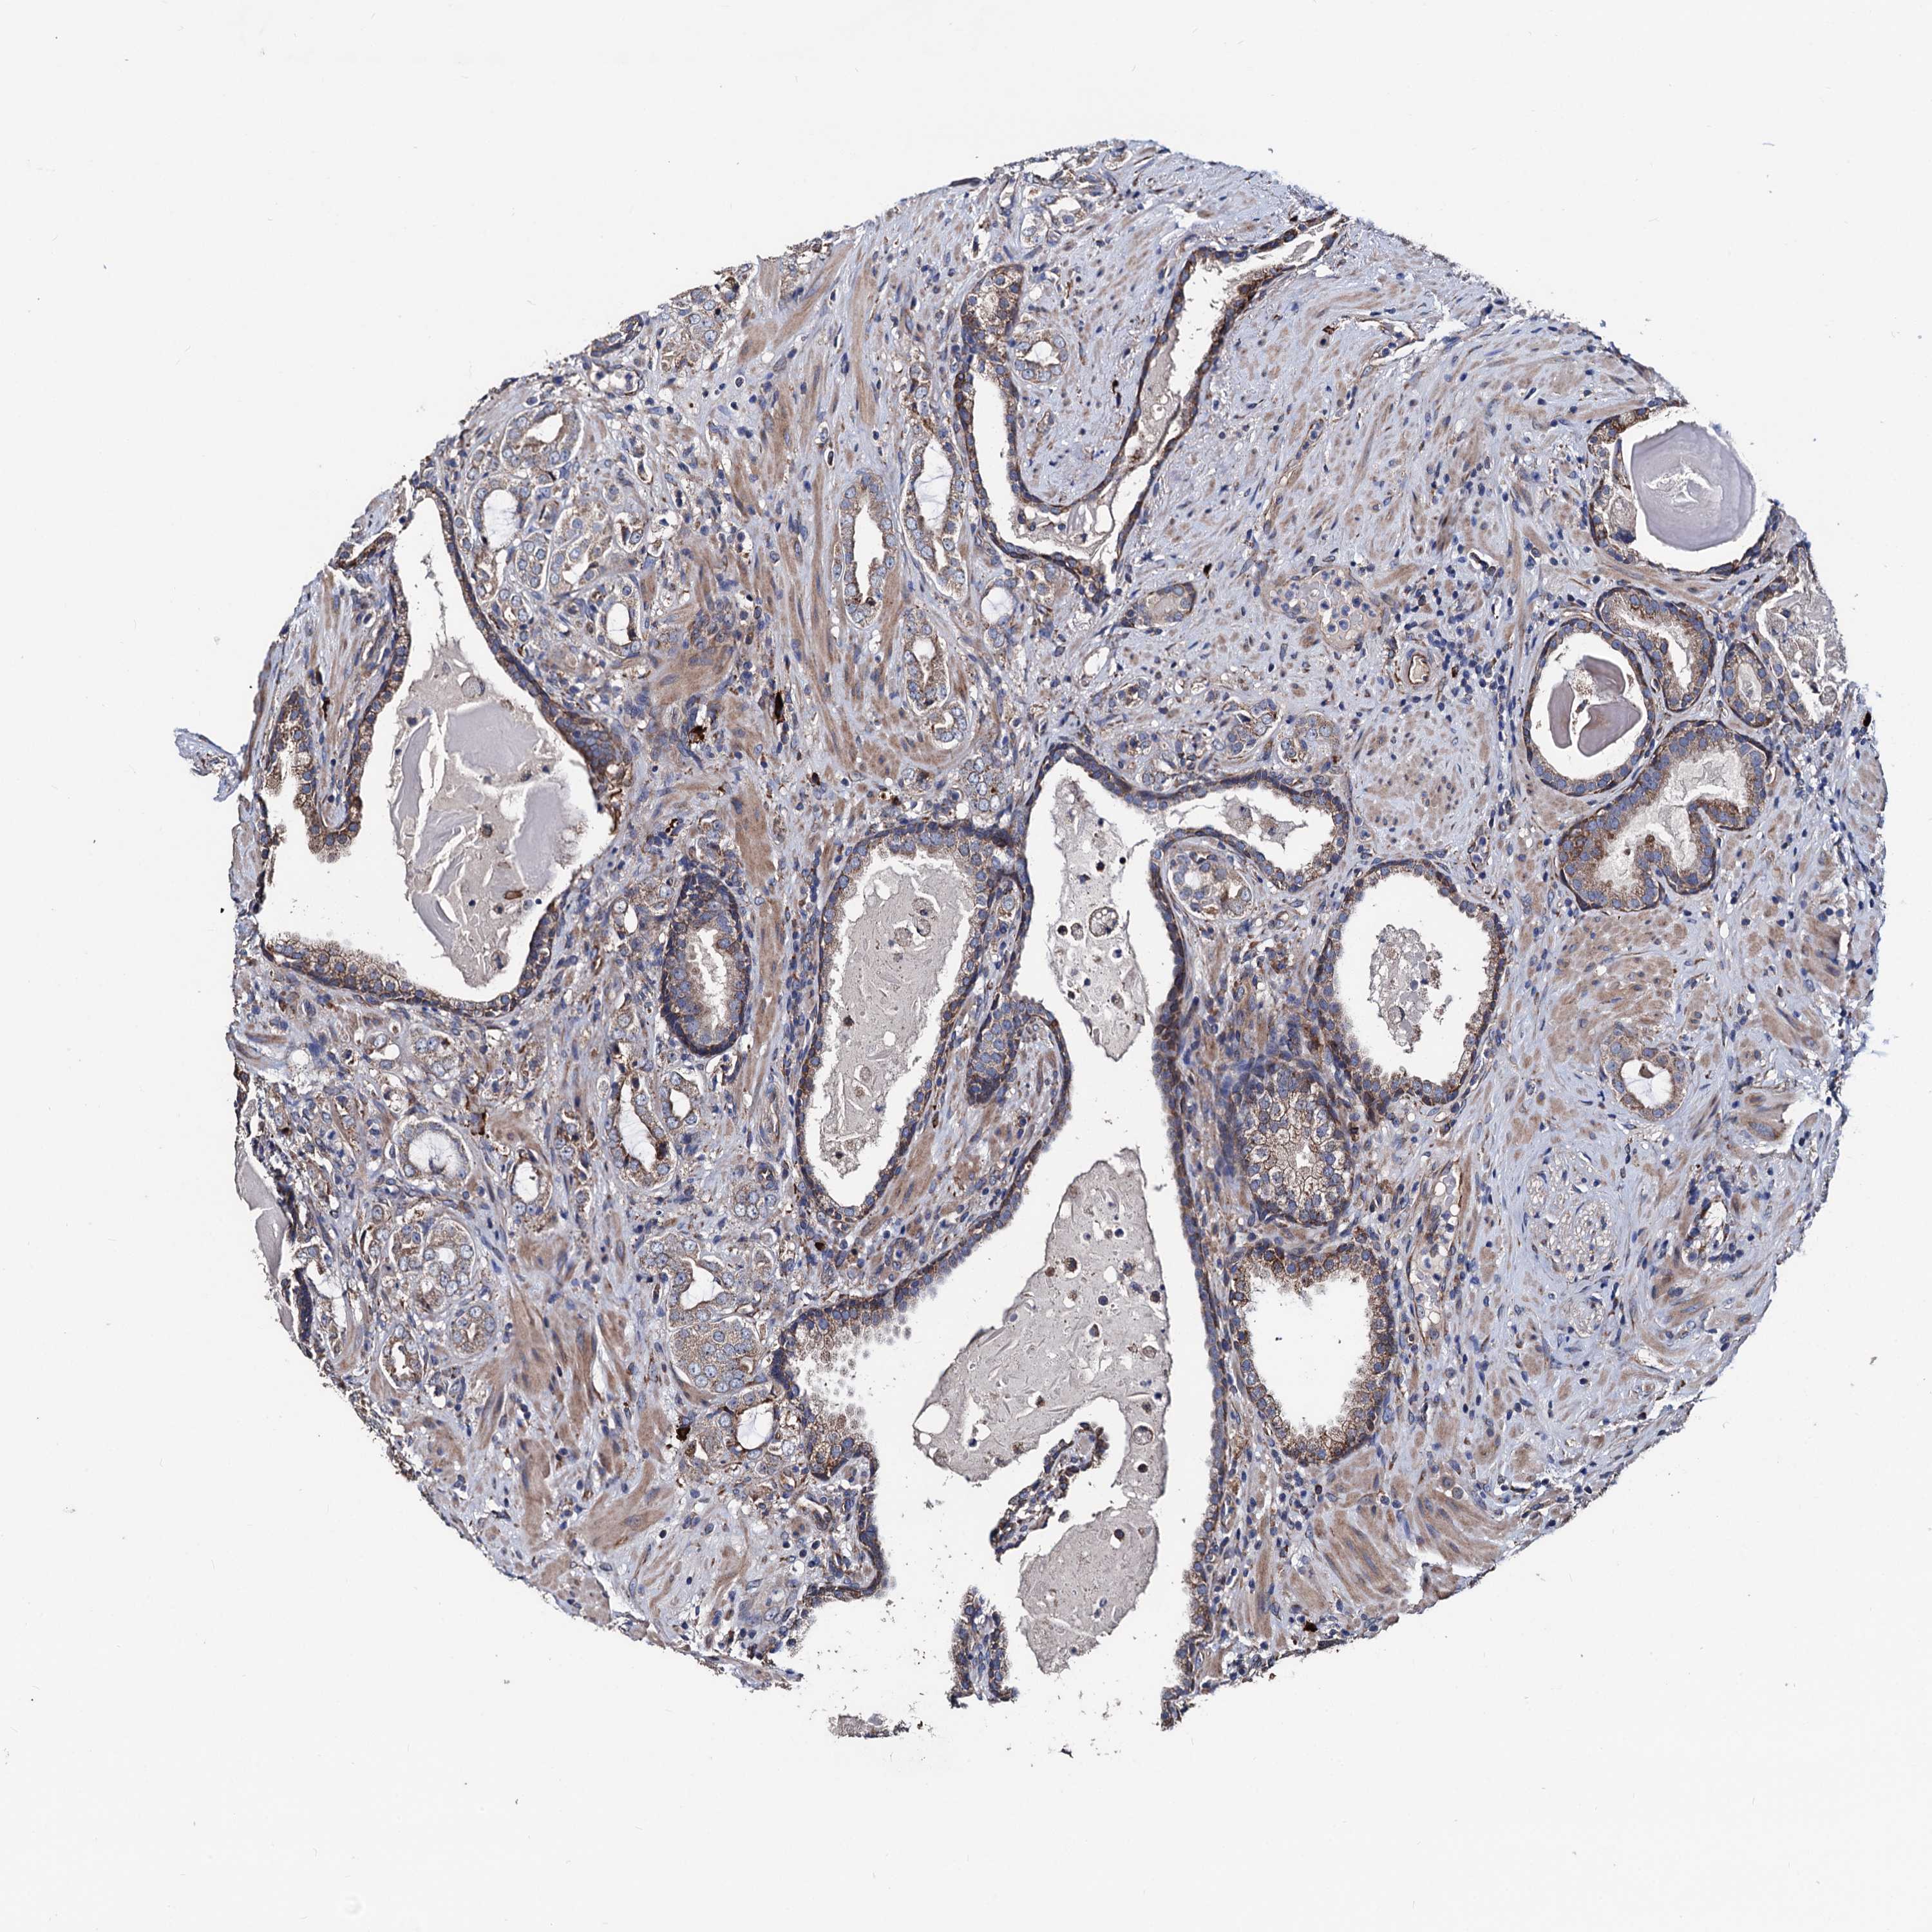

PROSTATE CANCER - Protein expressioni

A mouse-over function shows sample information and annotation data. Click on an image to view it in a full screen mode. Samples can be filtered based on level of antibody staining by selecting one or several of the following categories: high, medium, low and not detected. The assay and annotation is described here.

Antibody stainingi

Antibody staining in the annotated cell types in the current human tissue is reported as not detected, low, medium, or high, based on conventional immunohistochemistry profiling in selected tissues. This score is based on the combination of the staining intensity and fraction of stained cells.

Each image is clickable and will lead to virtual microscopy that enables deeper exploration of all samples and also displays staining intensity scores, fraction scores and subcellular localization as well as patient and tissue information for each sample.

Antibody HPA039089

Staining

High

Medium

Low

Not detected

Intensity

Strong

Moderate

Weak

Negative

Quantity

>75%

75%-25%

<25%

None

Location

Nuclear

Cytoplasmic/membranous

Cytoplasmic/membranous,nuclear

Adenocarcinoma, NOS

Adenocarcinoma, High grade

Adenocarcinoma, Low grade